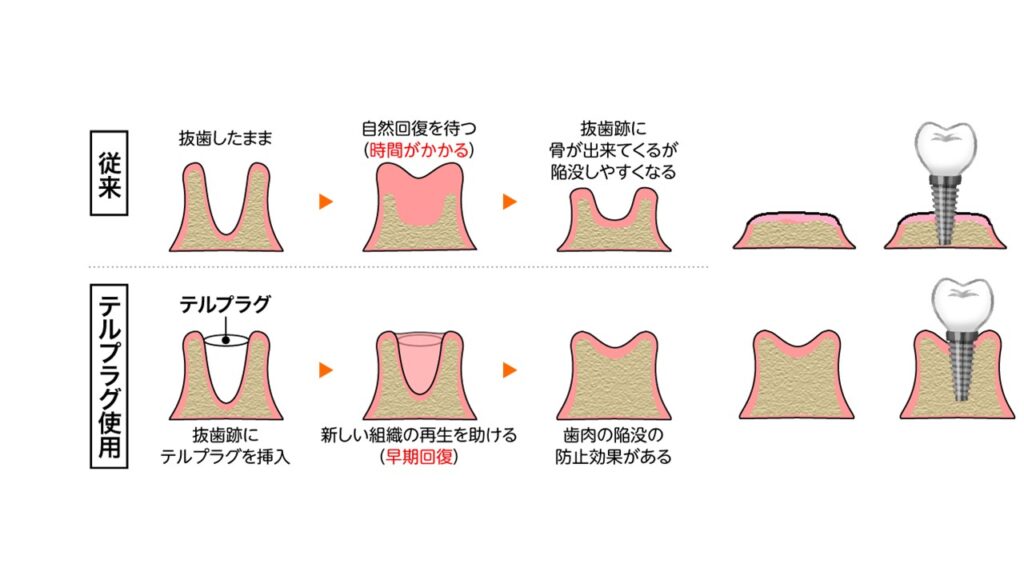

歯槽骨が露出した抜歯創へ充填し、止血、迷入防止等の創面保護ならびに肉芽形成を促す抜歯創用保護材です。原料に抗原性の少ないアテロコラーゲンを使用したスポンジ形態の製品で、抜歯創に充填しやすい形状をしており、無菌製品のため直ちに使用できます。熱処理による架橋のため、コラーゲン本体の生体親和性を損なうことがありません。

歯を抜いたままだと、周りの骨が吸収されて縮んでしまう